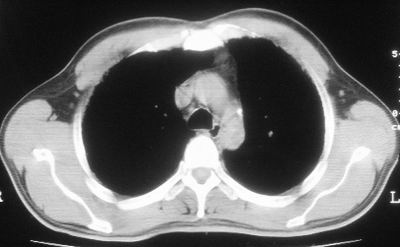

患者,男,44岁,糖尿病4年余,近期消瘦、乏力。化验检查:总胆红素26.33(参考值:5.1-17.2u mol/l),直接胆红素:6.4(参考值:0-4.3u mol/l),谷-丙转氨酶(alt):843(参考值:<40u/l),hbsag(+),抗hbs(-),hbeag(-),抗-hbe(+),抗-hbc(+)。

1\\粟粒性肺结核可能性大,支气管肺泡癌不排除

2\\少量腹水

诊断:癌性淋巴管炎.

考虑肺结核,少量腹水.

1.双肺急性粟粒型肺结核;2.少量腹水.